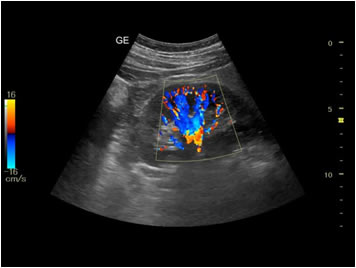

Abdominal Ultrasound

Used for scanning the abdominal organs to check for any disease condition. Such abdominal organs include the gallbladder, liver, spleen, intestines, kidneys, and tumors or masses in the abdomen.